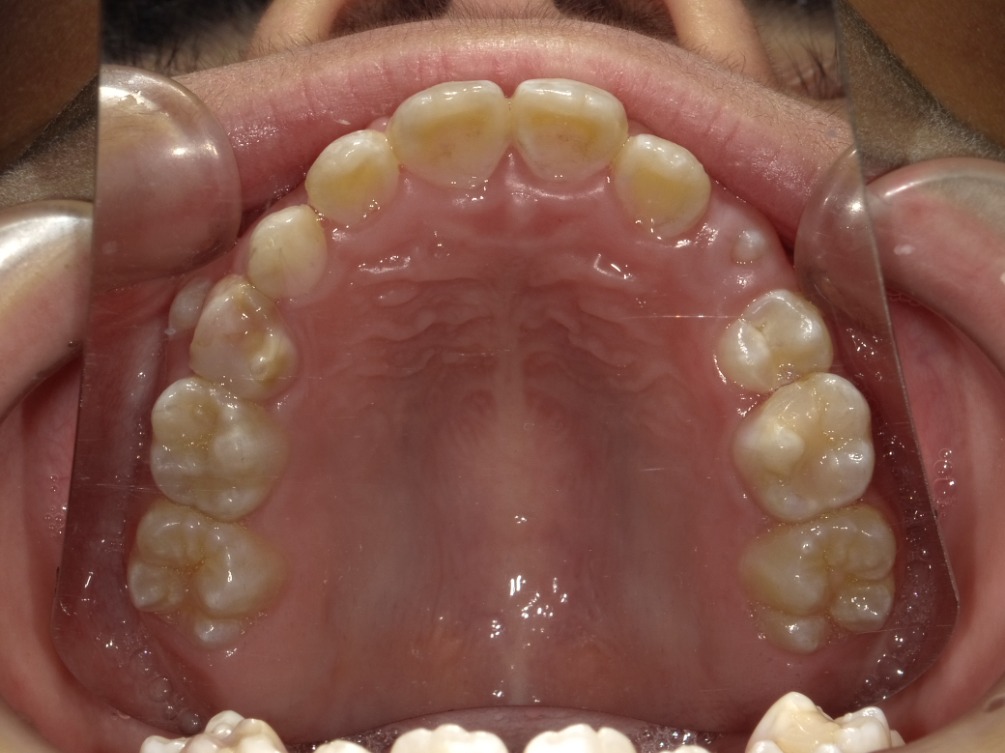

上顎

| 治療内容 | インビザライン・ファースト |

|---|---|

| 治療詳細 | 反対咬合や叢生、開咬を整えるために、歯の表面にアタッチメント(白い突起)をつけました。 また、顎間ゴムと呼ばれる引っ掛けるゴムの補助装置も用いて治療を行いました。 |

| 患者情報 | 10代 男性 予防矯正から移行 |

| 主訴 | 受け口 |